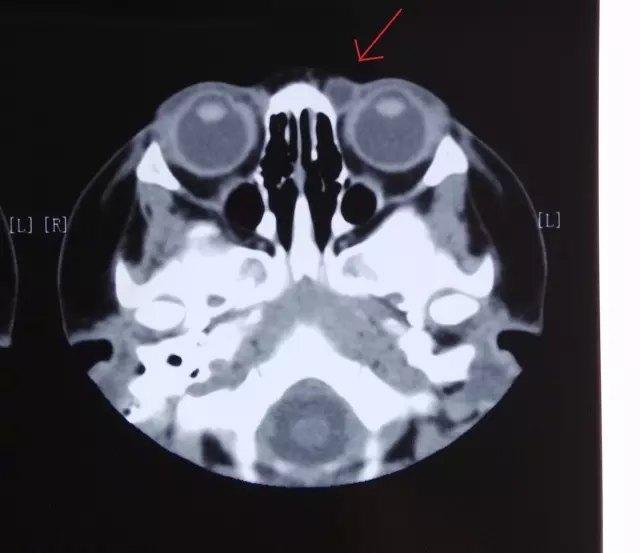

表皮样囊肿是儿童最为常见的一种良性的眼眶肿物,常常好发于眉弓或鼻根附近,

表皮样囊肿虽然非常柔软,但可以造成明显的骨凹陷,将来即使手术后,骨头的凹陷也仍然存在,由于不会自行消失,因此,一行诊断,多数还是建议早期手术治疗